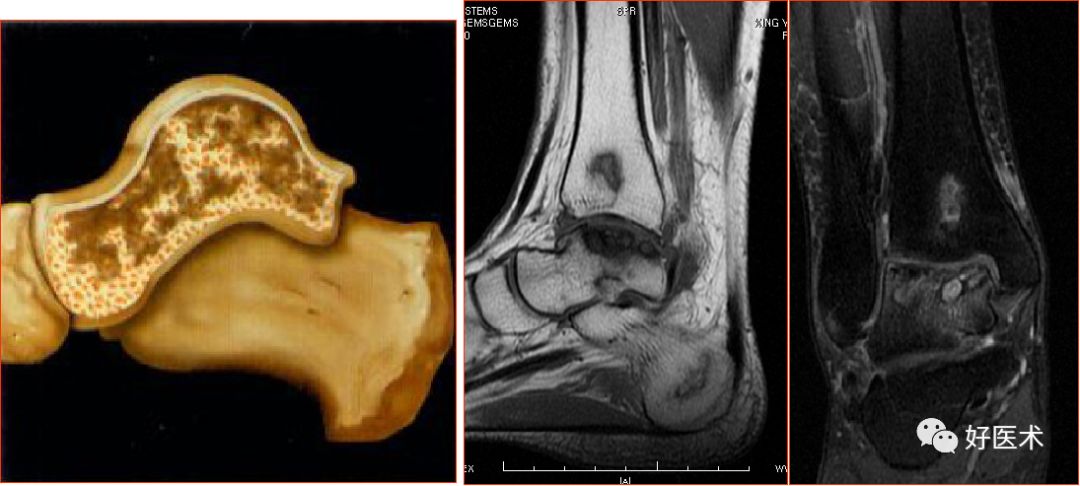

六、其它病变

三角骨综合征(距骨三角综合征)

足底腱膜炎(跖腱膜炎)

正常足底腱膜

足底腱膜炎MRI表现

足底腱膜炎:注意跟骨内侧结节的局限性水肿

踝管综合征

距骨骨缺血坏死,胫骨骨梗死

跗骨窦综合征